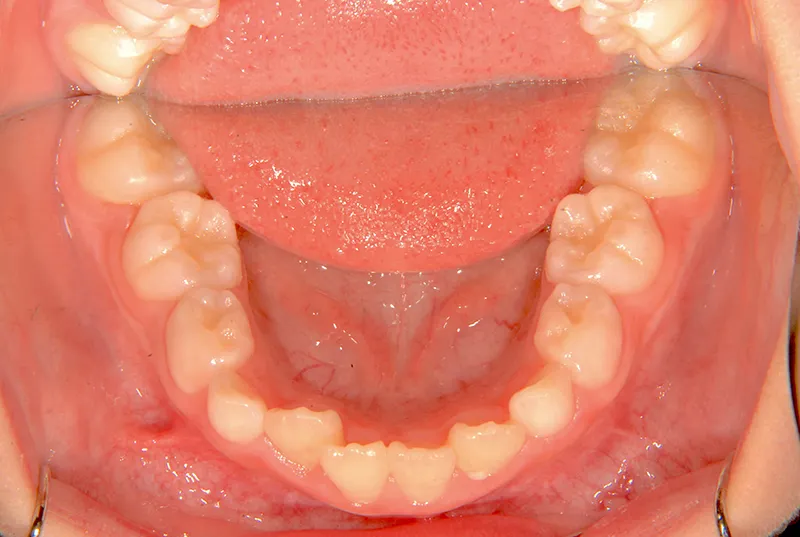

上の歯も下の歯も歯が生えるスペースが少ない為ガタガタしています。

前歯同士が上下で付き合わせる様に噛み(切端咬合)、

その横の歯は上の歯が下の歯の後ろにきて噛んでいる状態です(反対咬合)

初診